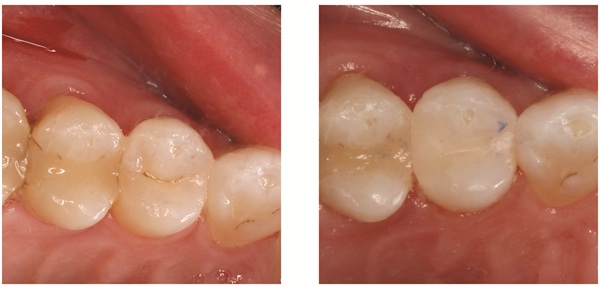

Fig. 1: Before and after restoration on tooth #10 using Voco GrandioSO 4U shade A1 cluster

As seen in Figure 1, we were able to seamlessly cover the dark yellow circle of dentin seen in the before photo while blending the composite covering the gingival two-thirds of the enamel to rebuild what was lost from erosion. Our patient was so thrilled with the outcome, that after we completed the required work on #10 and #12 (Fig. 2), she asked if she could have her other four Class V restorations on #7–9 completed at her next visit. With one small filling we gained big trust with a patient that began her visit with fear and anxiety and created a lasting, positive impression. Note that this was done fast with only one shade, yet you can see a gradation of shade blending over the entire tooth. Once cured we simply shaped and polished and she was asking for more.